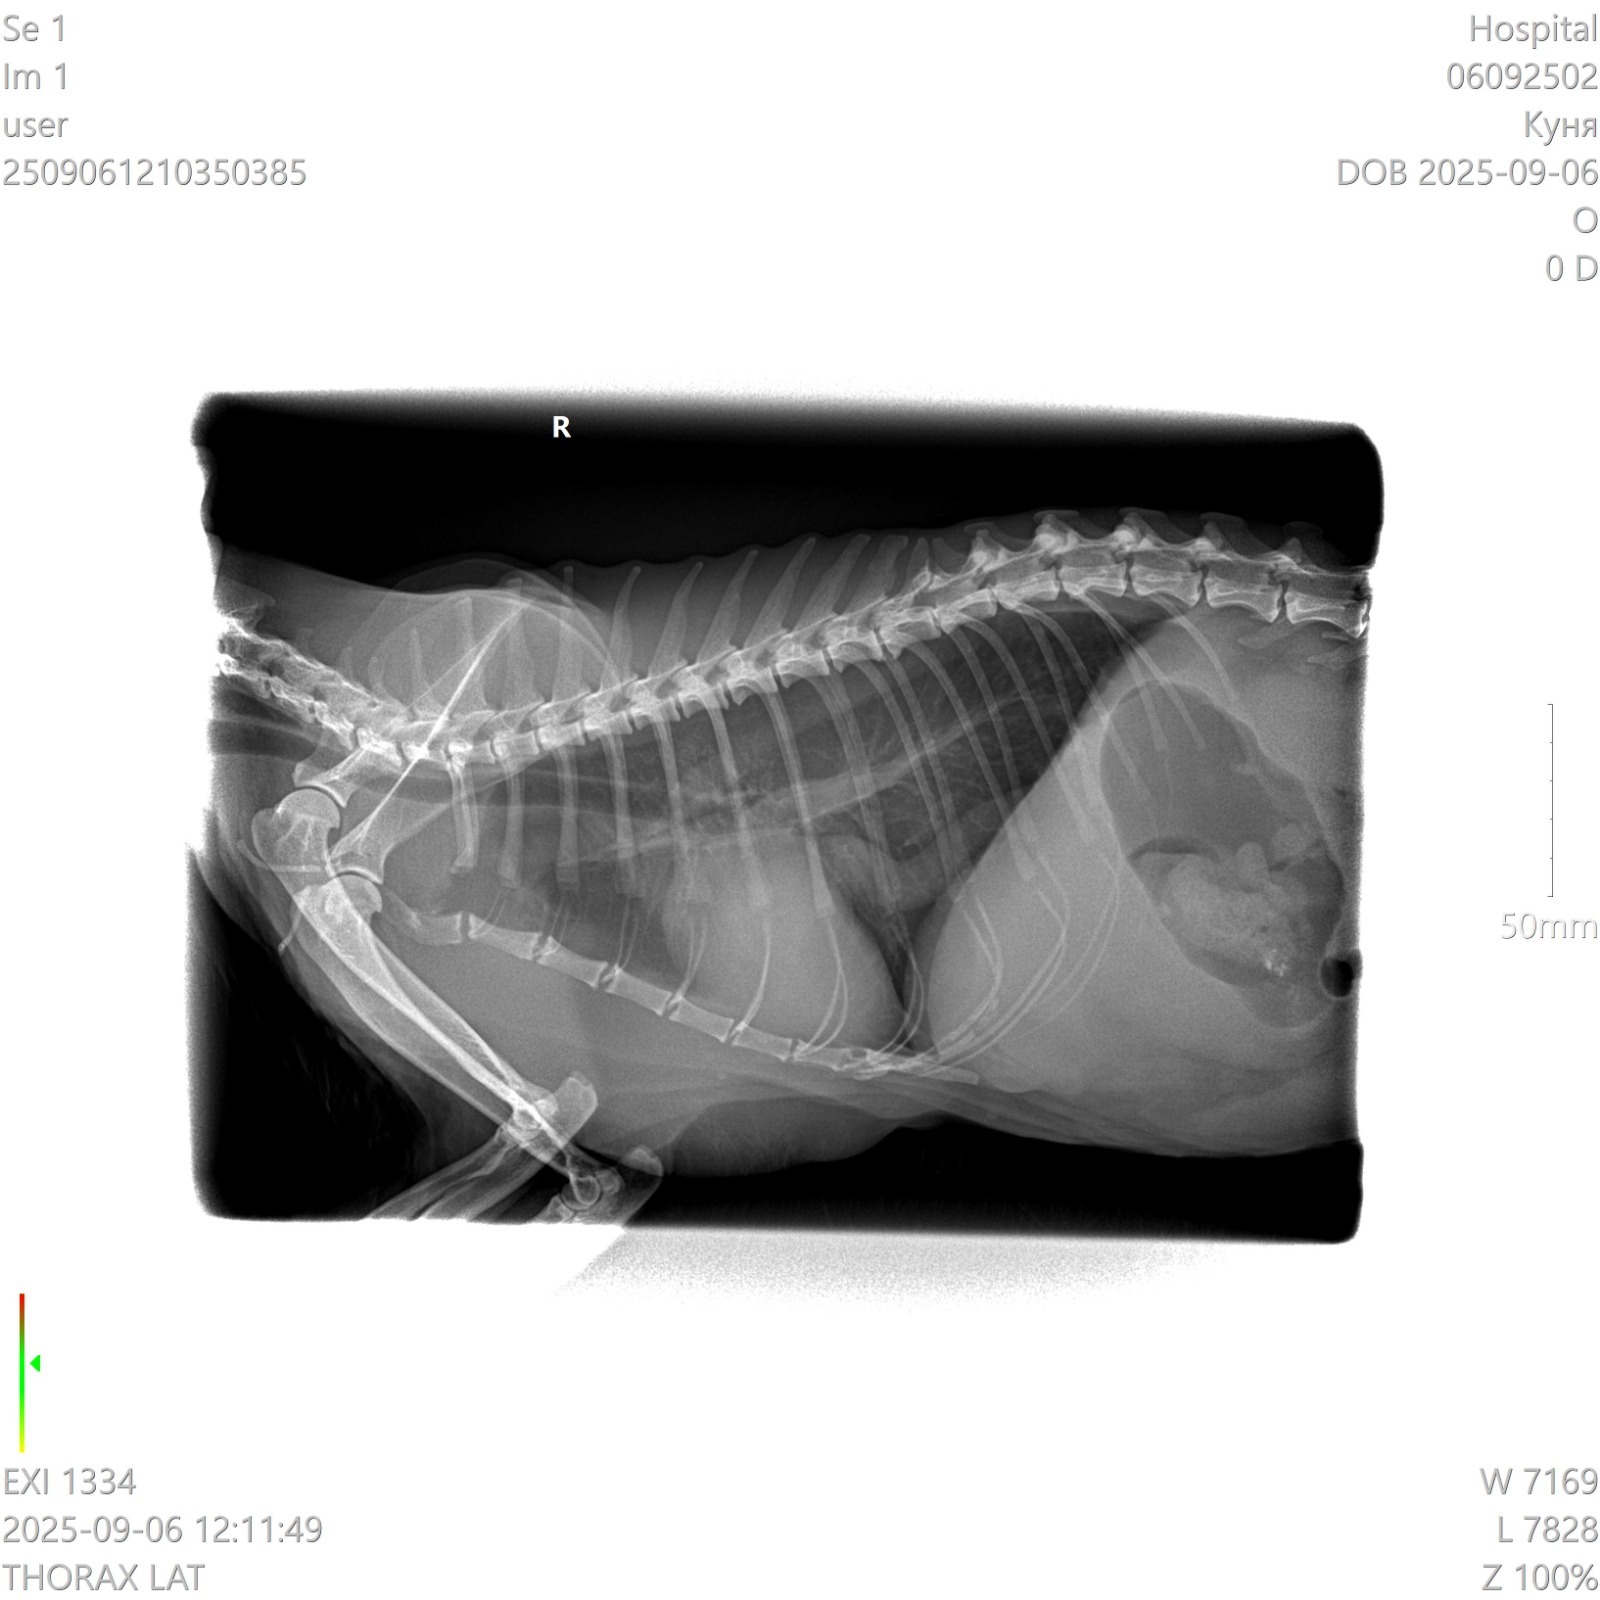

У кошки опухла левая часть грудной клетки.

Сделали рентген. Сказали что это не легкие, а какое-то новообразование. Что это может быть? У кошки тяжелое дыхание, почти не ест и не пьёт, приходится кормить через силу.